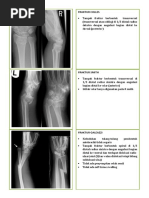

Tunah Bt kawi

Foto wrist joint dextra :

 Tampak fraktur pada 1/3 distal os radius dextra disertai angulasi fragmen fragmen fraktur bagian

distal ke arah dorsal

 Sela dan permukaan sendi dalam batas normal.

 Tidak tampak lesi litik maupun sklerotik.

KESAN :

Fraktur pada 1/3 distal os radius dextra disertai angulasi fragmen fragmen fraktur bagian distal ke

arah dorsal (coles fracture)